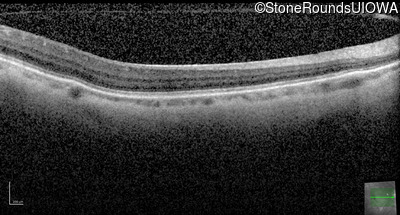

AD Familial Exudative Vitreoretinopathy (IIIE2b)

Age at visit: 32 years

This 32 year old woman has had subnormal acuity (right eye worse than left eye) since very early childhood.

Diagnosis & molecular findings

AD Familial Exudative Vitreoretinopathy TSPAN12 Arg50Trp AG(G)>TG(G)   AD